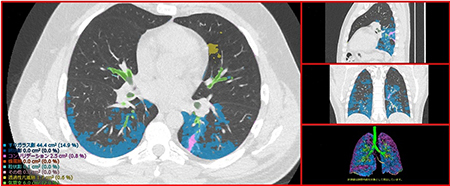

富士フイルムの間質性肺炎の定量化技術は、AI技術を用いて設計したソフトウェアが、CT画像から肺野内の気管支、血管、正常肺、網状影やすりガラス影、蜂巣肺など肺の7種類の病変性状を識別し、自動で分類・測定することで、間質性肺炎の病変を定量化するもの。さらに、肺野内の病変の分布と進行状態を詳細に確認できるよう、肺野を12の領域に分割し、その領域ごとに、病変の容積と割合を表示する。